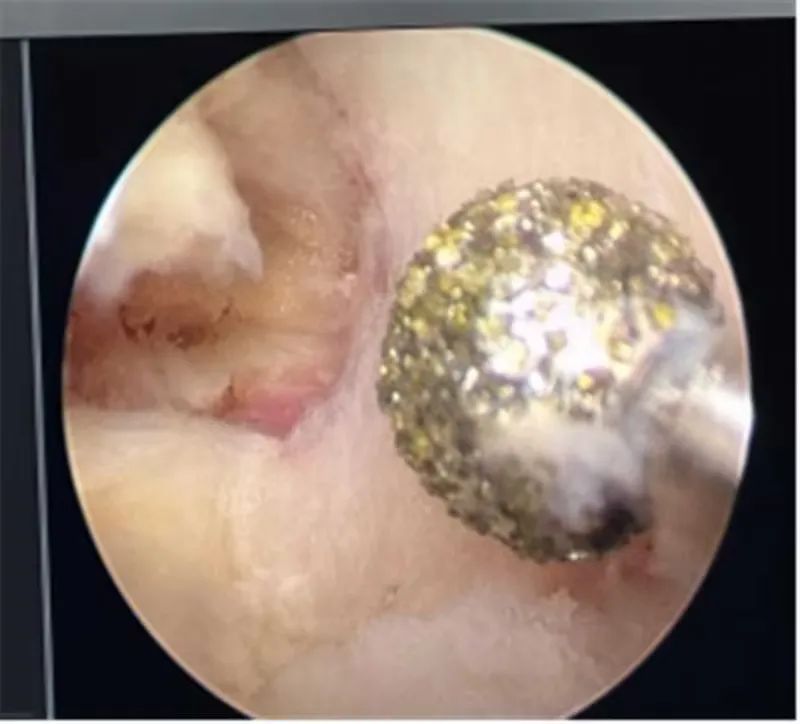

37岁的辛某某,腰臀部酸胀1年,左下肢放射性疼痛1月,曾在当地医院诊断为腰椎间盘突出症给予理疗、射频消融等治疗后症状缓解不明显,近1月来出现左下肢放射性疼痛,从臀部放射至大腿后侧、膝关节、小腿外侧,疼痛进一步加重,严重影响到患者的日常生活。不能下地活动,为寻求进一步治疗,来到市星元医院就诊。经过专科查体及影像学辅助检查,患者被诊断为腰椎间盘突出症、腰椎管狭窄症。邢永军主任医师团队综合评估患者病情,结合患者年龄、椎管狭窄程度、椎间盘退变程度、椎间隙高度等各项指标,经与患者充分沟通,开放手术创伤太大,单轴内镜受灵活性所限,不一定能够达到手术目的,“AUSS是传统脊柱手术内镜化方案,兼具开放手术和内镜手术的优势,且创伤比双通道的UBE手术更小,是目前最好的选择!,制定了“AUSS关节镜辅助单孔脊柱手术”的治疗方案。术中,医生通过可视化内镜辅助对患者狭窄的椎管进行减压、突出椎间盘进行摘除,对破裂的纤维环进行缝合,提高患者术后生活质量,术后患者恢复良好。下肢放射性疼痛完全消失。

AUSS技术即关节镜辅助单切口脊柱手术,是目前新兴的脊柱内镜技术,结合了UBE技术与孔镜技术的优点,是单轴内镜技术的延续、UBE双通道技术的改进、开放手术内镜化的体现,是将工作通道与观察通道置于同一软性切口内,具有减压范围广、操作空间大、定位简单、透视少等特点,30度关节镜,视野范围广,镜头360度自由转动,减少操作盲区;不同内镜技术的结合:关节镜的三角操作以及后路同轴内镜的同轴摆动、旋转,以及非同轴旋转技术。